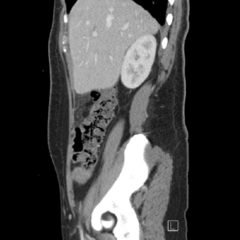

We present a case of a 51-year-old previously healthy man who presented to the ED complaining of chest pain that had resolved prior to arrival, and a mild headache. His vital signs were notable for hypotension, but physical exam was unremarkable. Chest x-ray revealed a borderline widened mediastinum. A standard ETTE was within normal limits, but additional SSNV demonstrated a dissection flap in the aortic arch. The patient was taken to the operating room for surgical repair 75 minutes after the ED ultrasound was performed; the operation was successful, and the patient was discharged to home post-operatively with good outcome.